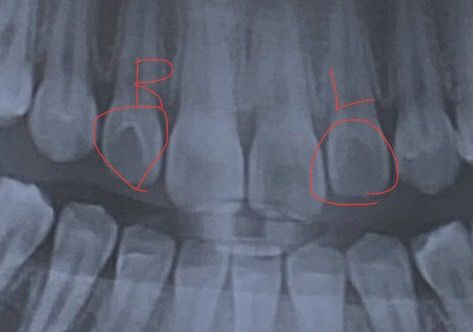

이틀전쯤 밥을 먹고 양치를 하다가 상악 측절치 중 오른쪽은 안쪽이 까끌거리고 왼쪽은 괜찮아서 충치 때문에 이빨이 파진 줄 알고 병원에 가서 진찰을 받았는데 그냥 이렇게 비대칭으로 태어난 사람이 있다고 설명해주시고 충치 때문이 아니라고 하셔서 스케일링만 받고 나왔어요. 육안으로 봤을 때도 색깔이 다르다거나 모양이 크게 달라보이진 않는데 오른쪽이 왼쪽보다 훨씬 깊게 파져서 그런지 혀로 만졌을 때 까끌거리고 깊으니까 신경쓰이네요ㅠㅠ 원래 이렇게 까끌거리고 깊게 파져도 괜찮은건가요? 평소에 전혀 안 느껴졌는데 최근에 갑자기 느껴지게 된거라 이상이 있는 것 같은데 없다고 하시니 답답하네요ㅠㅠ 증상을 느끼기 전에 찍어놓은 엑스레이 사진 첨부합니다!

• 1번 째 사진

사진으로 보더라도 선천적인 치아 이상으로 보여지며 검사 상 큰 문제가 없다면 걱정하지 않으셔도 됩니다. 다만 홈이 깊다면 그 만큼 음식이 많이 저류할 수 있으므로 양치 및 구강 관리는 신경써서 해주셔야 합니다. 또한 주기적으로 치과 방문을 해주시면 도움이 됩니다.

상악측절치가 많이 패여 잇다면 치내치일가능성이 높습니다. 크게 문제가 되는건 아니니 걱정하지 않으셔도 될것같습니다.

측절치는 형태변이가 종종 있는 치아입니다 삽모양측절치의 양상인것 같고 특별히 병적인 것은 아닙니다